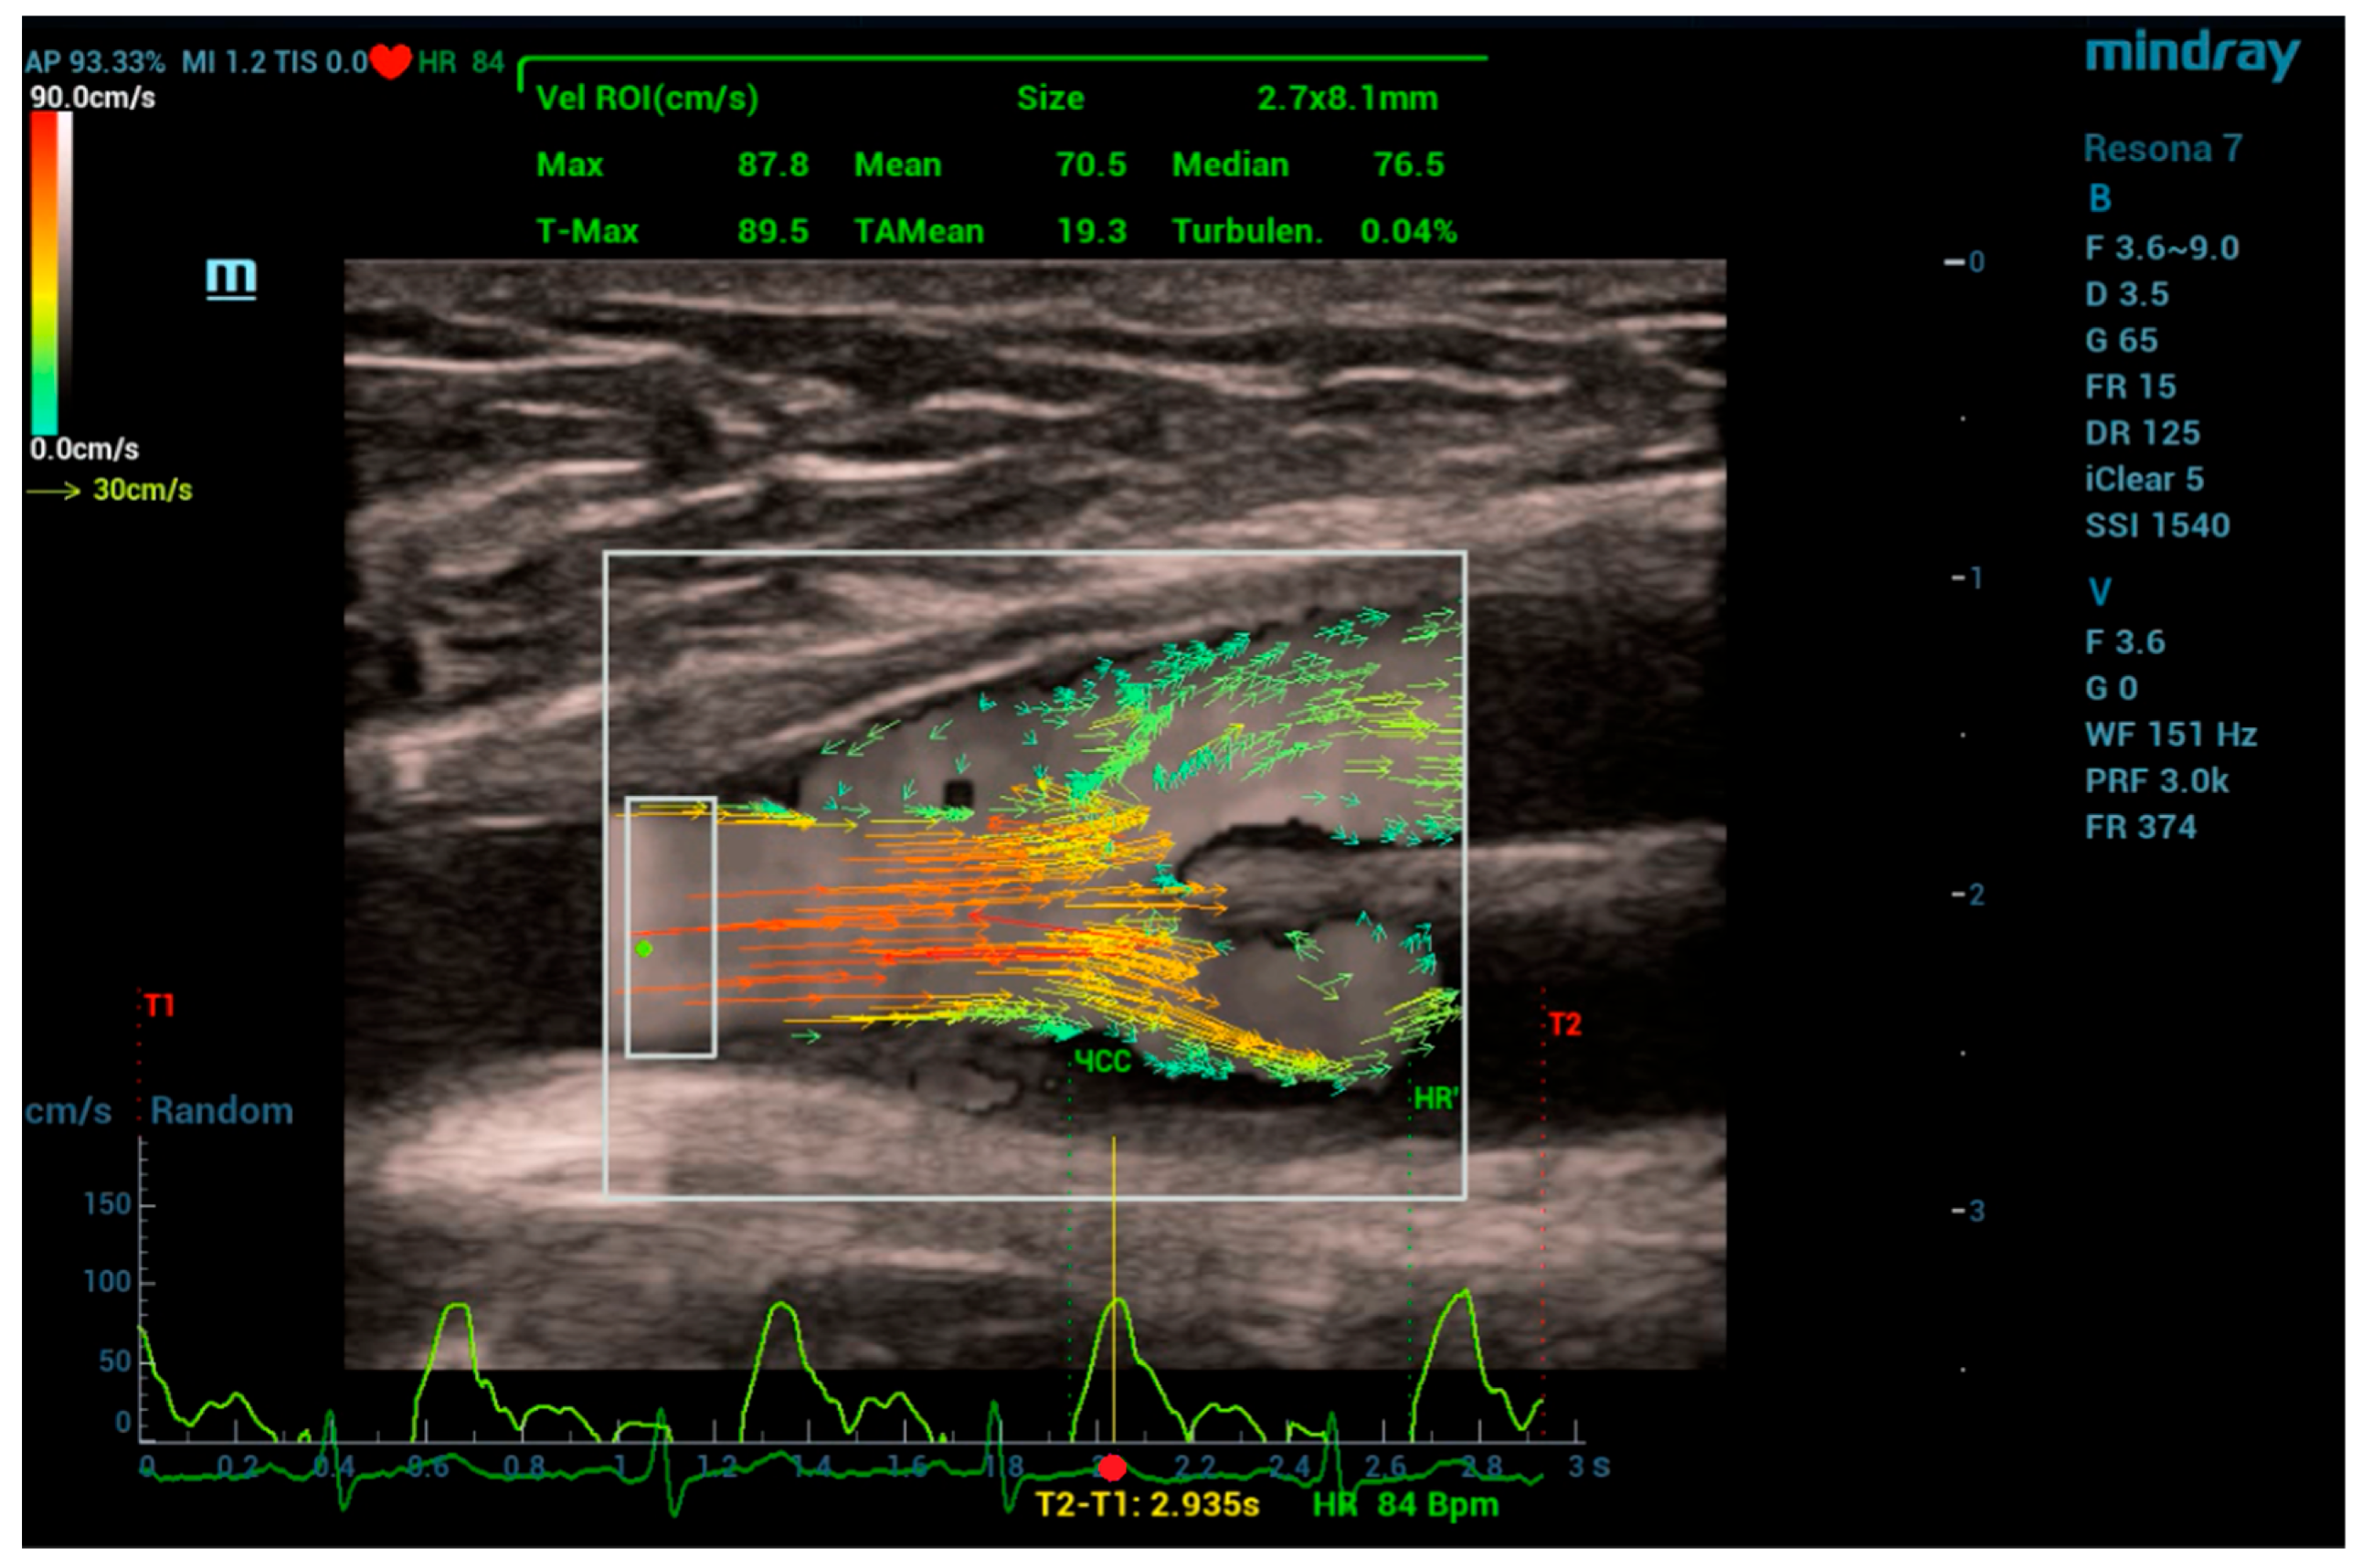

During the measurements, the scanning plane of the ultrasound transducer coincided, as it was possible, with the middle longitudinal plane of the anastomosis areas under examination. Figure 4 shows the window of the V Flow program with a 2D vector velocity field directly at the site of the graft branch from the CFA. Here, the scanning window, highlighted with a white frame, has dimensions of 20 × 27 mm. The results of the vector field processing for the region of interest (ROI), highlighted with a white frame with dimensions of 2.7 × 8.1 mm, are visualized by the velocity curve (light green curve) at the point of maximum velocity in the ROI (green dot), being synchronized with the electrocardiogram signal shown at the window bottom. The upper part of the window displays the values of automatically calculated flow velocities for the ROI. The following notations are used here: Max—instantaneous maximum velocity, T-Max—maximum velocity during recording time (T1~T2), Mean—instantaneous average velocity over ROI, TAMean—average velocity over recording time (T1~T2), Median—instantaneous median velocity, Turbulen—velocity pulsation parameter, and Size—ROI size.

Figure 4.

V Flow program window when placing the scanning window at the site of the graft branch from the patient’s common femoral artery.